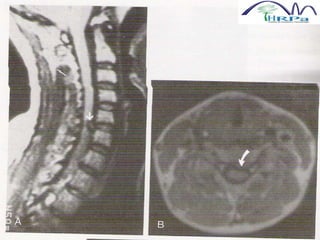

DIAGNÓSTICO

 A PRIMEIRA OPÇÃO PARA EXISTÊNCIA

OU NÃO DE COMPRESSÃO RADICULAR

POR HÉRNIA DISCAL CERVICAL É: RMN

 TAXA DE FALSO-NEGATIVOS É ALTA

 QUANDO NÃO DISPOMOS, PODE SE

USAR A TC E MIELOGRAFIA

 MIELOGRAFIA: FALHA DE ENCHIMENTO

EXTRADURAL

 TC: CANAL CERVICAL COM MENOS DE

10MM DE DIÂMETRO SAGITAL MÉDIO É

ESTENOSE ABSOLUTA E 10-13MM É

RELATIVA